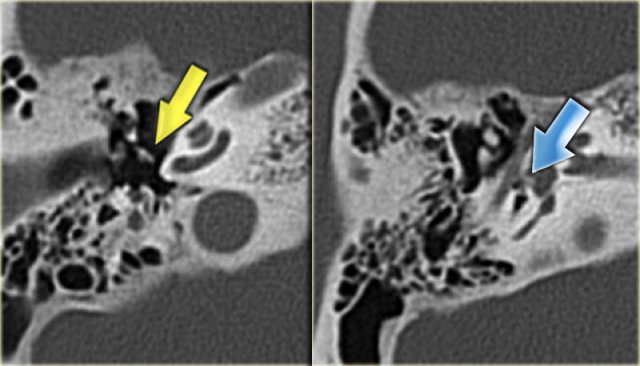

On the left images of a 14-year old boy with bilateral sensorineural hearing loss.

Calcification of superior semicircular canal on the left (yellow arrow).

Right ear for comparison (blue arrow).

On the left coronal images of the same patient.